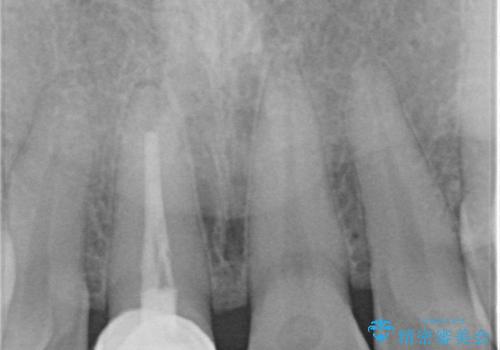

- 数年前に前歯のセラミック治療を行い、そのやり替えを希望して来院された患者様です。

先端が欠けてしまっていて、色も少し不自然な印象があります。

空隙がある歯並び改善のため、矯正治療も提案しましたが希望せれず、隣の歯も一緒に被せものにして、

大きさをそろえることも希望されなかったため、一本だけやり替えていくととしました。